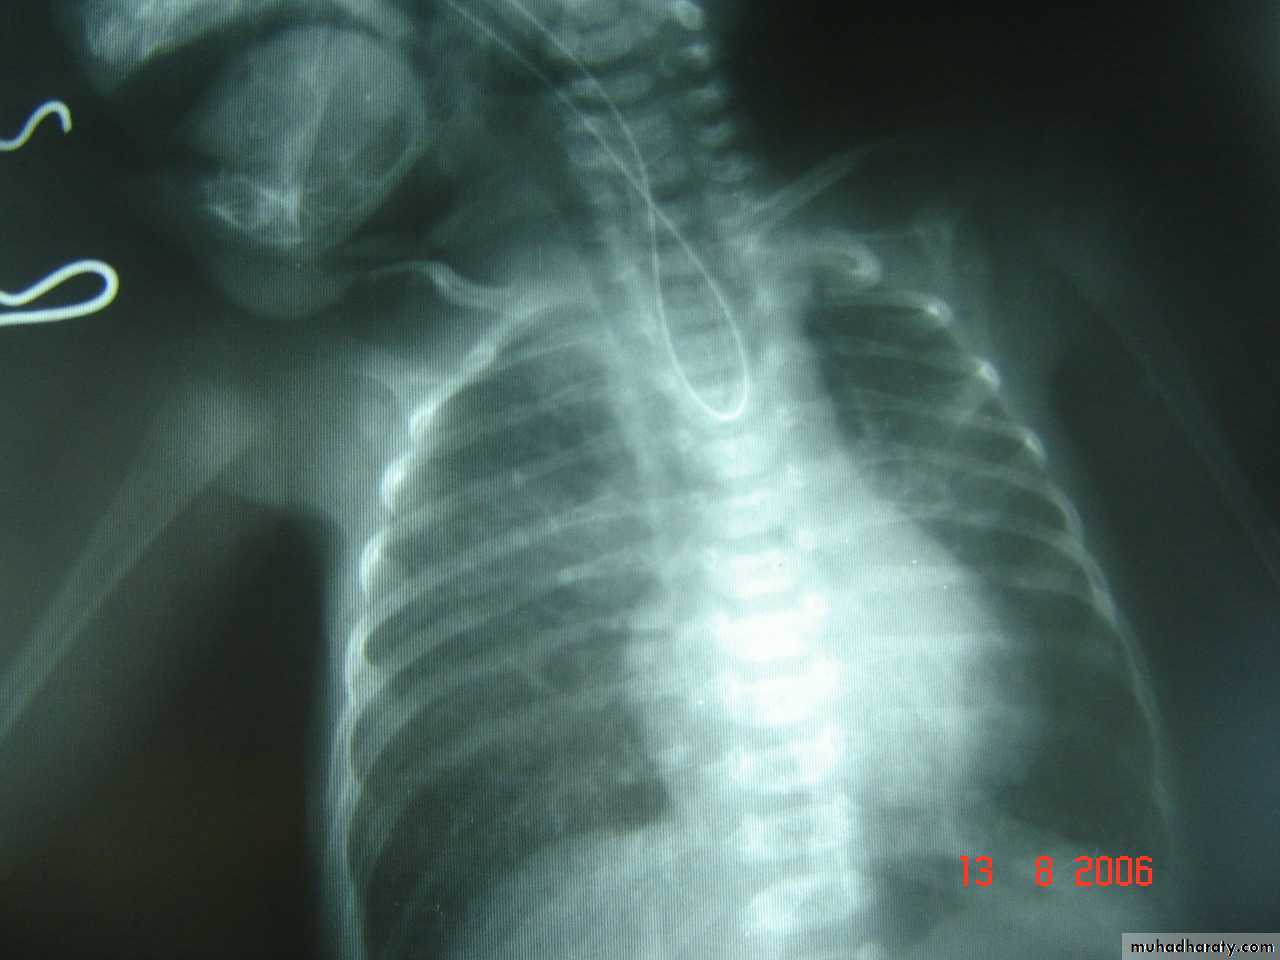

A 2 week old boy presents with history of constipation, abdominal distension and bilious vomiting. The pictures show the operative findings and radiographic investigation done for him.1. What is the diagnosis?2. What is the underlying pathology for this condition?3.Describe the findings in all slides.4. What other investigations used to reach the diagnosis?5. What are the steps of management for this condition?